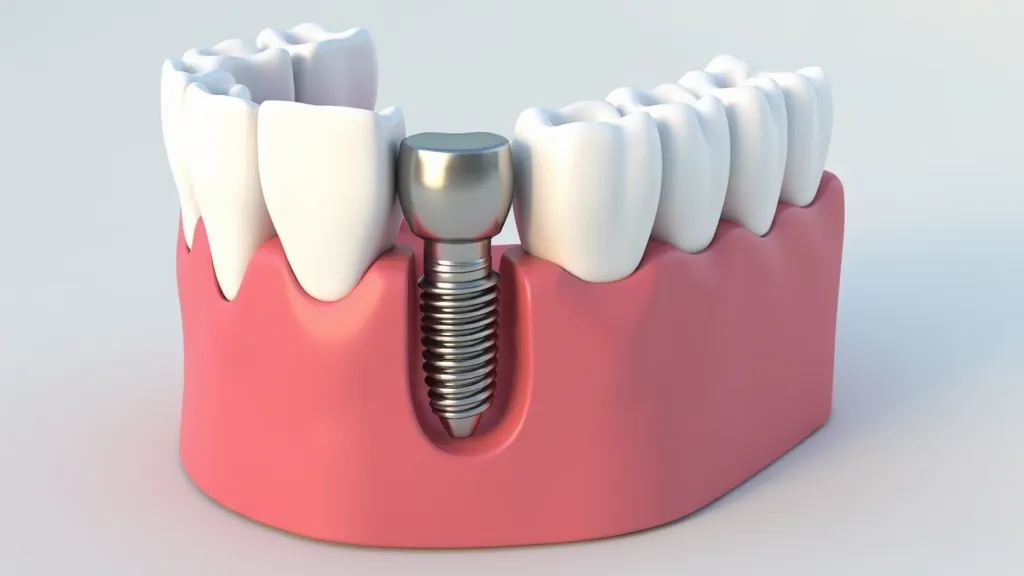

Full mouth dental implants are a transformative solution for individuals facing extensive tooth loss. They not only restore functionality but also enhance aesthetics, allowing for a confident smile. However, the cost can be a significant barrier. This guide offers insights into affordable options, including clinical trials.

Typically, the cost for full mouth dental implants ranges significantly based on the materials used, the complexity of the procedure, and the dental practice's location. However, options exist to obtain these services at a lower cost, including promotions like full mouth dental implants for $99 or eligibility for clinical trials.

Full mouth dental implants are a restorative dental solution that replaces all missing teeth in the upper and/or lower jaw using implants.

The cost can vary widely, typically ranging from $20,000 to $40,000, depending on several factors. However, affordable options may be available, including clinical trials.